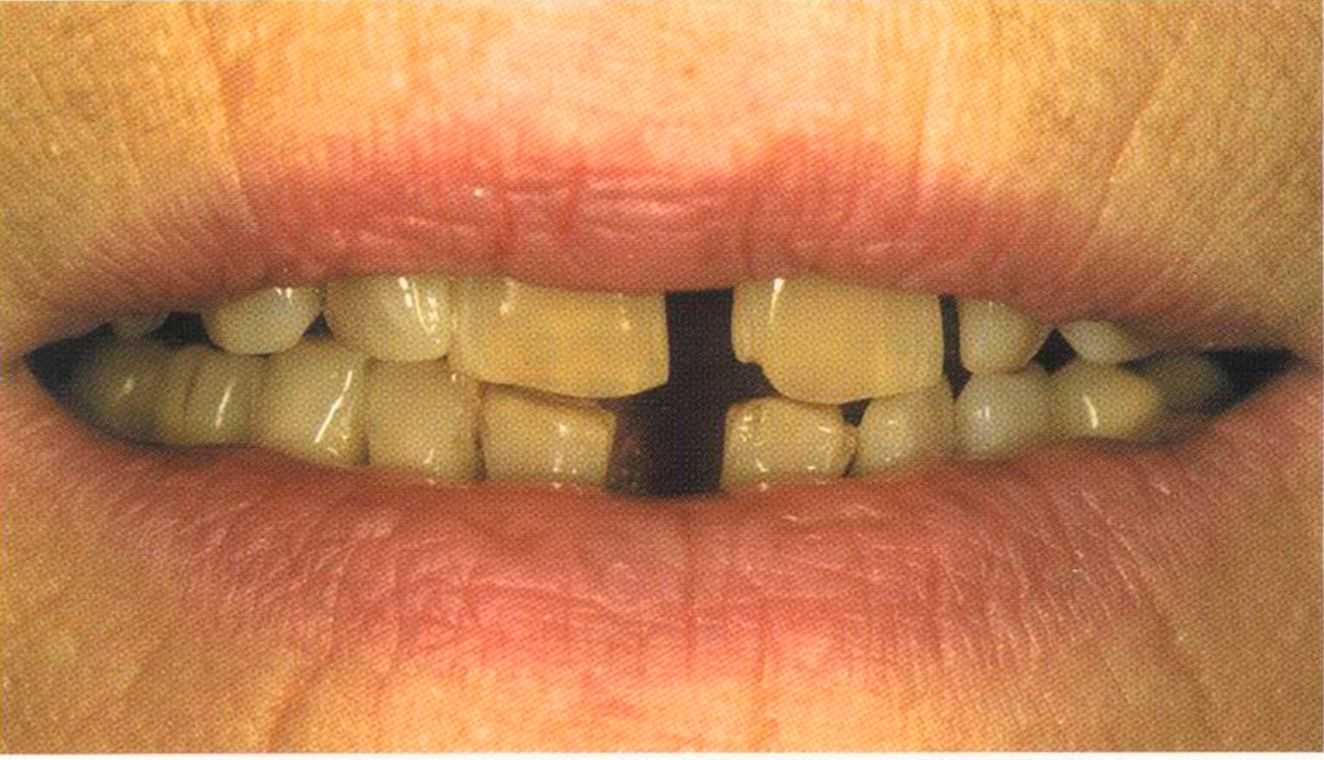

Вспомним, как все начиналось.

Окончательный результат и естественный цвет губ. Женщина была очень счастлива и довольна своим новым внешним видом. Наконец мечта осуществилась — нет больше этих щелей на видимом участке. Всей нашей команде было очень приятно видеть радость в ее глазах.